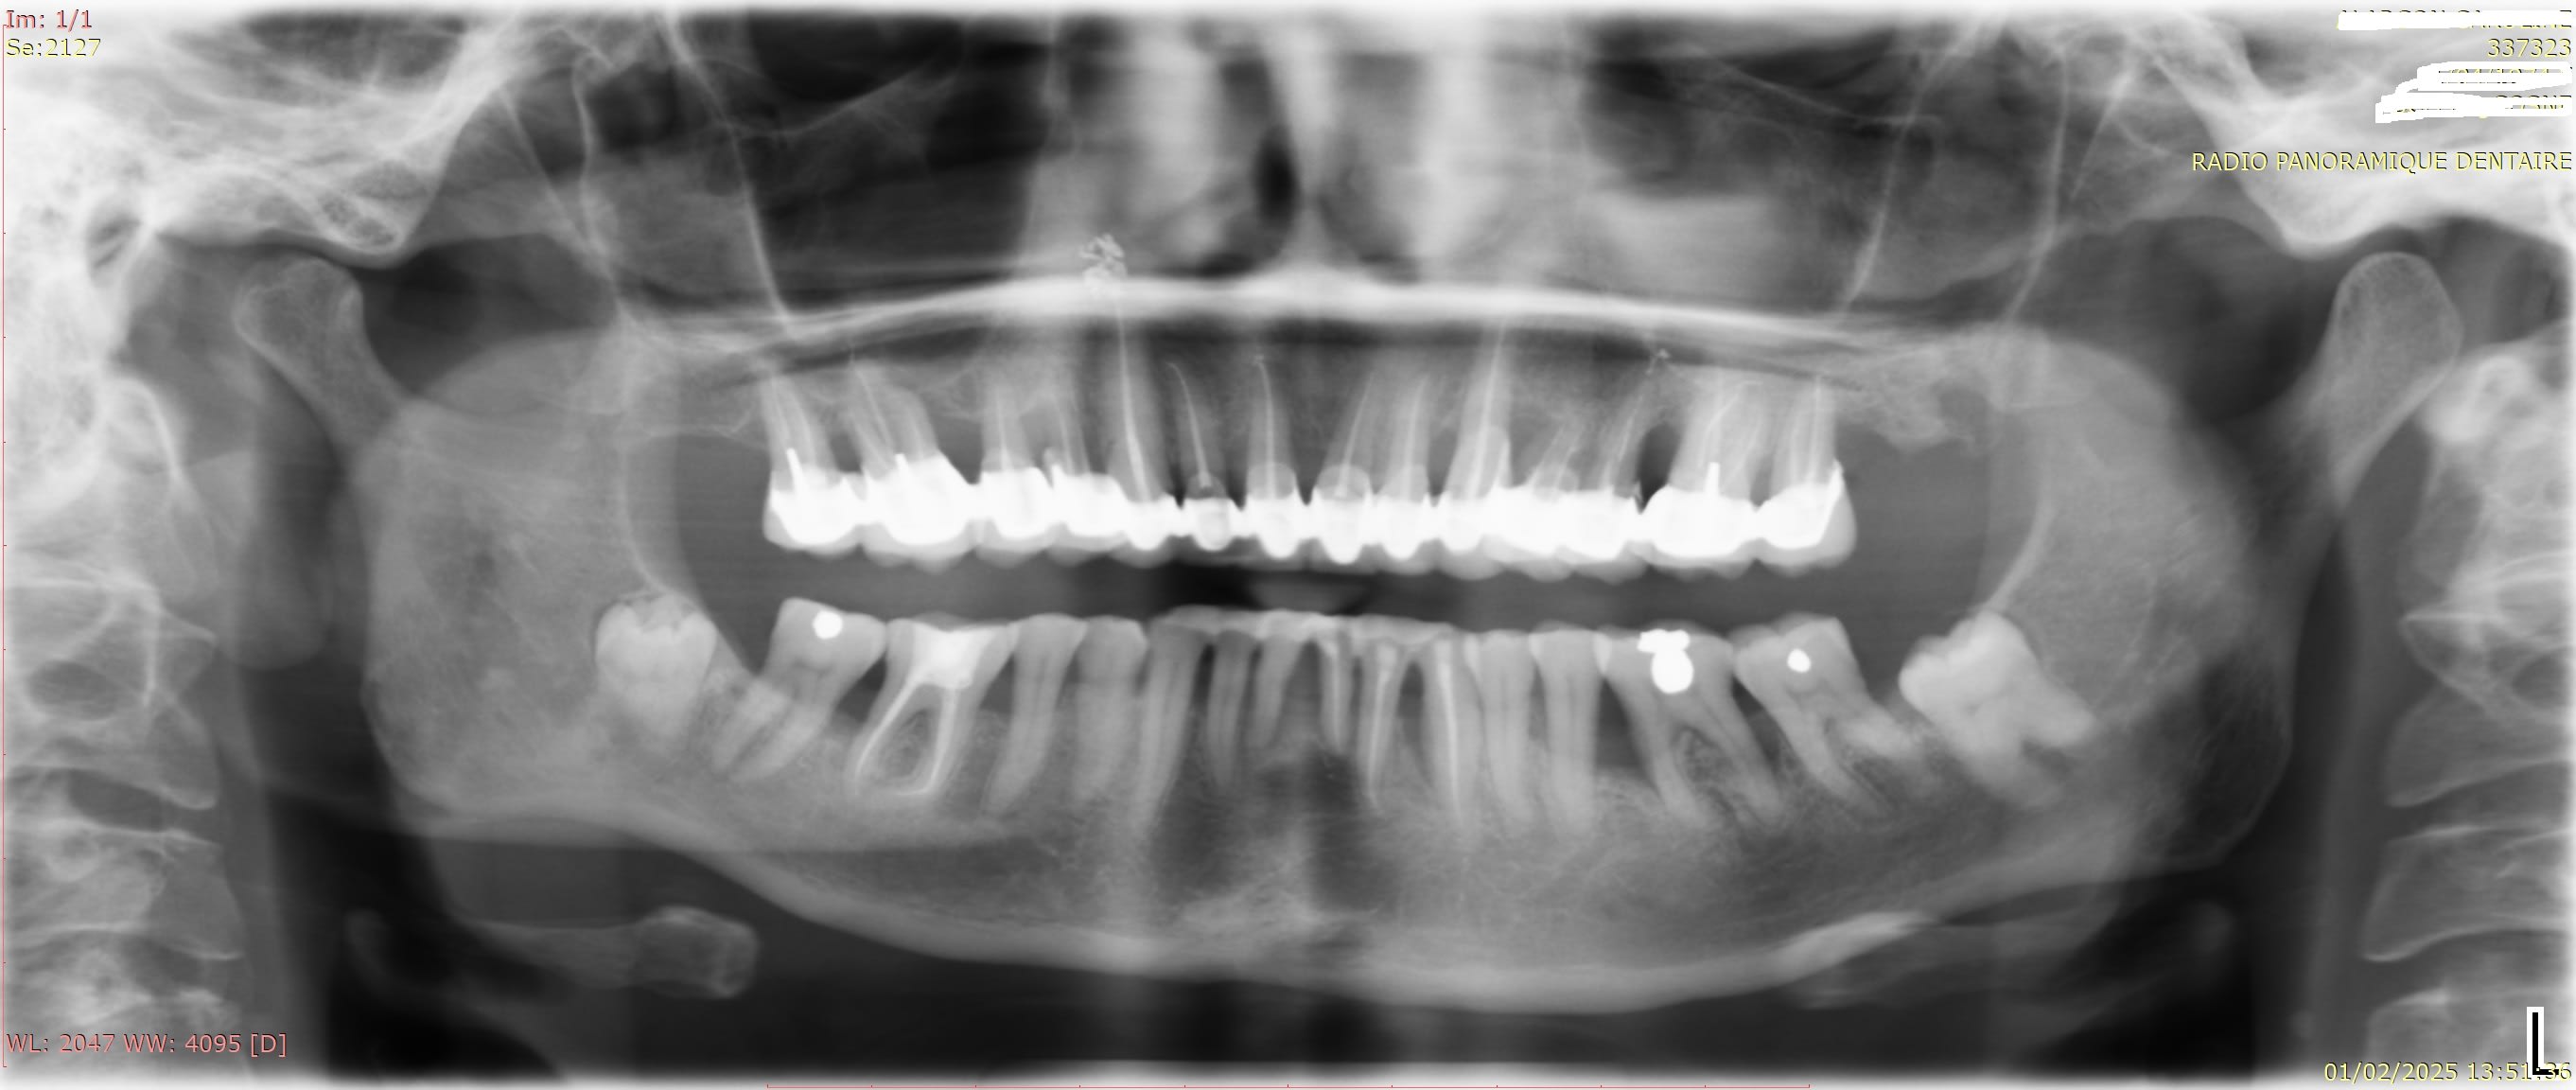

des nouvelles, pour le moment ça va plutôt pas mal, légère amélioration du contour gingival sur 11 / 12...

Exemple ici, le haut est "nettoyé " ce qui d'ailleurs n'est pas une assurance à 100 pour 100, de ne jamais avoir de douleurs chaud / froid... mais ça rassure quand même, et pour le bas, je ne vais pas tout dévitaliser, puisque j'espère avoir une partie prothèse beaucoup plus simple (ccc molaire et petite atelle pour les antérieures)